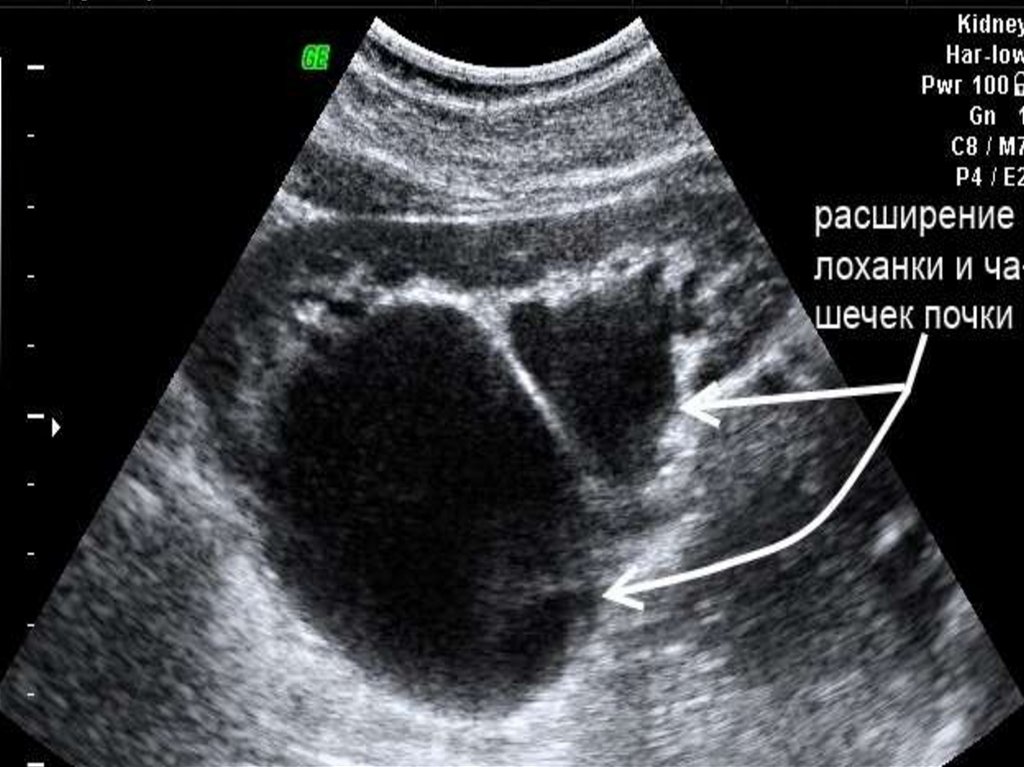

• Пиелоэктазией называют

расширение внутренней

полости почки, которое, как

правило, может быть

рассмотрено как начальная

стадия гидронефроза почек.

• Расширение может

захватить всю чашечнолоханочную систему и тогда

можно говорить о

каликопиелоэктазии.

Сдавление этих органов

ведёт к расширению

чашечно-лоханочной

системы (ЧЛС) почек. Та

13. Диагностика

• Клиника и анамнез

• Анализ мочи и

биохимический

анализ крови.

• УЗИ-диагностика

• Урография и

цистография.

• КТ